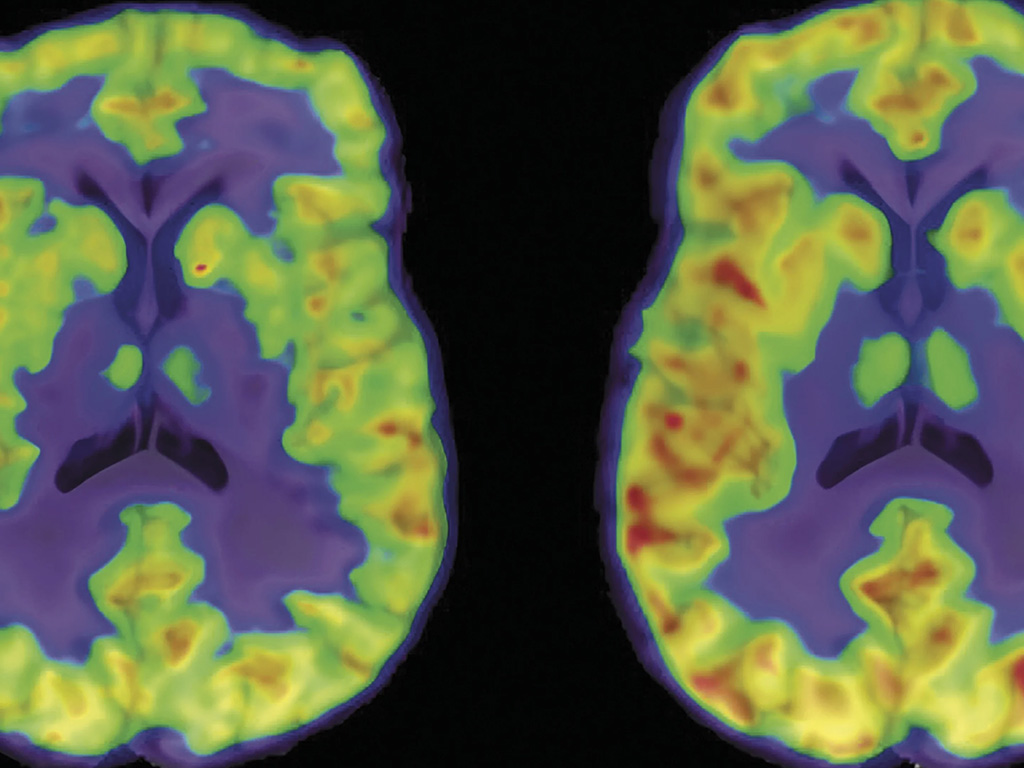

PET images of the brain

How Novel Treatments Target the Neurobiology of Depression

Holmes leads a parallel line of research investigating how ketamine brings about its antidepressant effects at the level of brain biology. Using positron emission tomography (PET), her team conducted the first study to measure ketamine’s effects on synaptic density in the living human brain. “We’re trying to visualize neuroplasticity in action—to see whether ketamine actually helps rebuild lost connections between neurons,” Holmes explains.